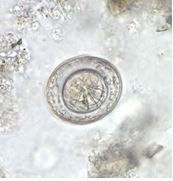

Hình 3: Trứng sán H. nana

H. nana là loài sán dải nhỏ nhất, con trưởng thành dài 15 – 44 mm, có khoảng 200 đốt sán. Đầu sán hình cầu, đường kính 0,25 mm, có 4 đĩa hút hình chén và một vòng móc với 24 – 30 móc. Đốt sán trưởng thành hình thang, dài 0,2 - 0,3 mm, ngang 0,8 - 0,9 mm, có một lỗ sinh dục, ba tinh hoàn tròn và một buồng trứng hai thùy. Đốt sán mang trứng có một tử cung hình túi, chứa 80 -180 trứng. Đốt sán già thường tan rã trong đường tiêu hóa và ít khi hiện diện trong phân. Trứng không màu, gần như trong suốt, hình bầu dục hoặc hình thuẫn, kích thước 40 - 60 μm x 30 - 50 μm. Vỏ trứng dày, gồm hai màng, chứa phôi 6 móc. Mỗi cực của màng trong có một chỏm tròn nhỏ, từ chỏm này xuất phát nhiều sợi treo nhuyễn, khúc khuỷu nằm giữa dịch genlatin sền sệt. Trứng có khả năng gây nhiễm ngay khi theo phân ra ngoài và có thể tồn tại đến 10 ngày ở môi trường bên ngoài.